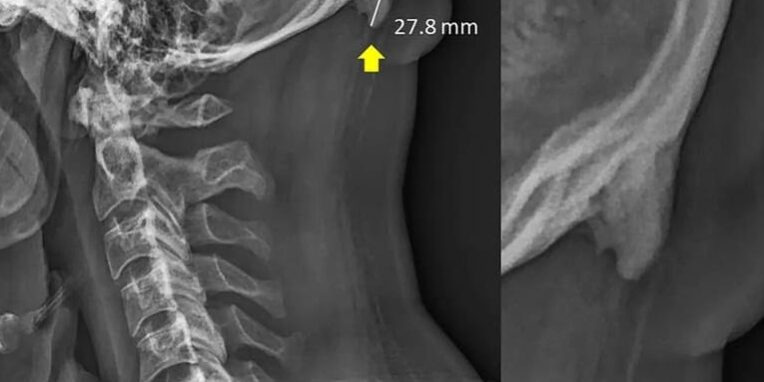

Researchers at the University of the Sunshine Coast in Queensland, Australia, have documented the prevalence of bone spurs at the back of the skull among young adults. (Scientific Reports)

New research in biomechanics suggests that young people are developing hornlike spikes at the back of their skulls — bone spurs caused by the forward tilt of the head, which shifts weight from the spine to the muscles at the back of the head, causing bone growth in the connecting tendons and ligaments. The weight transfer that causes the buildup can be compared to the way the skin thickens into a callus as a response to pressure or abrasion.

The result is a hook or hornlike feature jutting out from the skull, just above the neck.

Part of what was striking about the findings, he said, was the size of the bone spurs, which are thought to be large if they measure 3 or 5 millimeters in length. An outgrowth was only factored into their research if it measured 10 millimeters, or about two-fifths of an inch. Click on the link below to find out more.